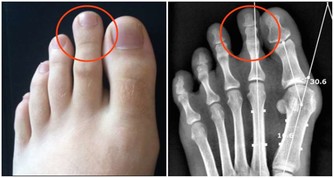

6、巨大胃黏膜皺襞症(Menetrier病):血清蛋白經巨大胃黏膜皺襞漏失,臨床上有低蛋白血症與浮腫,約10%可癌變。